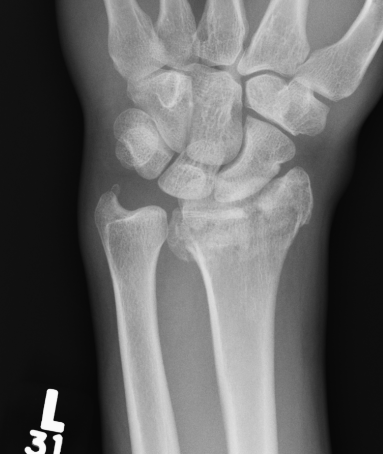

Distal radius fracture with shortening and dorsal tilt

Articular incongruency > 2 mm

Sigmoid notch disruption and DRUJ instability